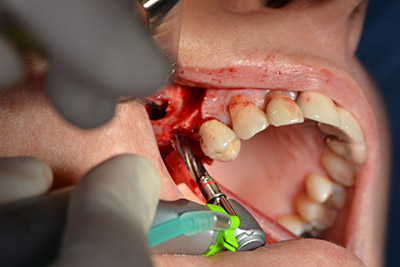

The classic incision (crestal, buccal relief) and the preparation of the mucoperiosteal flap enabled a good overview.

Sky implants (bredent) were used in this case. The surgical protocol of these, specify pilot drilling at about 1200 rpm (Fig. 9).

The following holes were drilled at a reduced speed of 300 rpm. The Implantmed demonstrated its true capability at this stage. The surgical protocol can be preset – the various positions can be selected simply by pressing the “P” position of the foot control (Fig. 10 to 11).